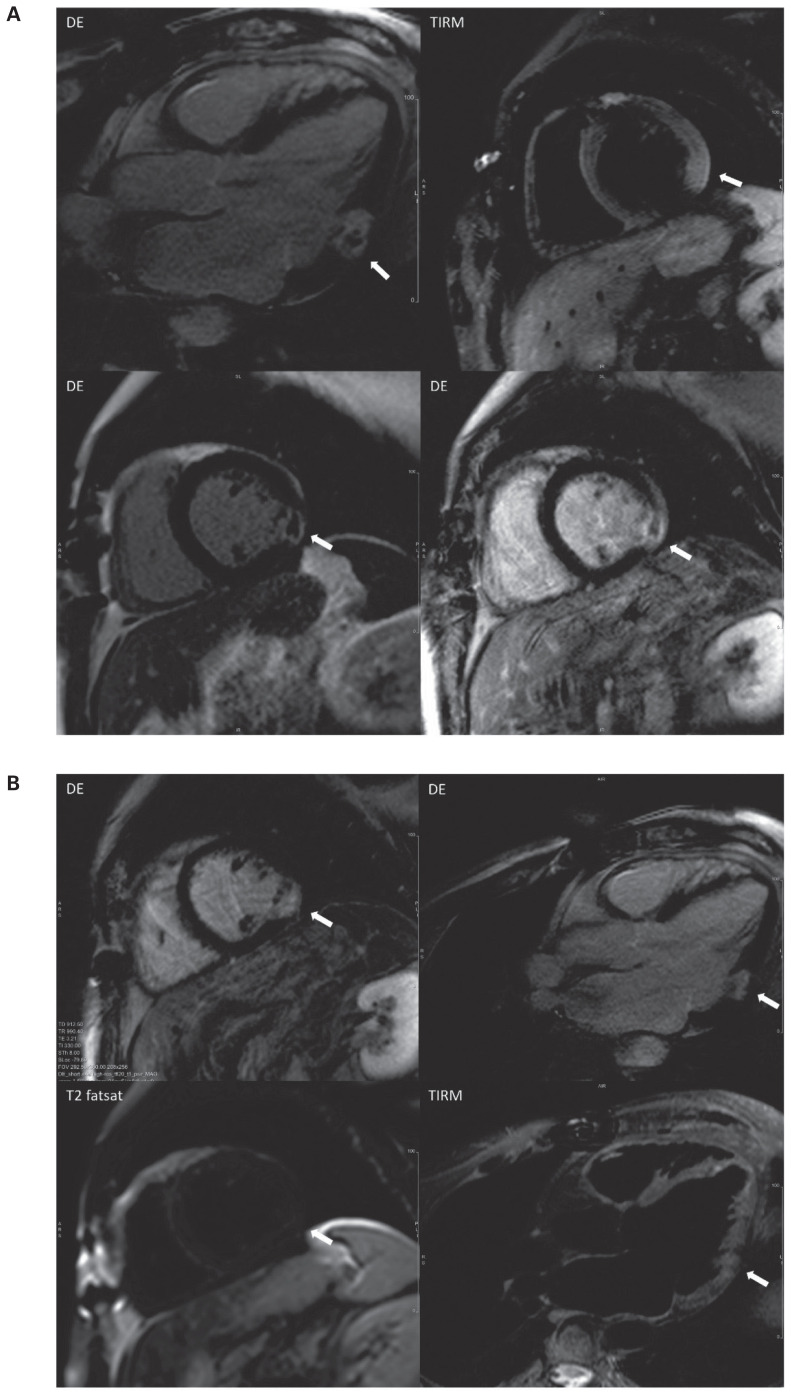

CMR-defined transmural myocardial infarction with area of microvascular obstruction in the MINOCA patient: How many undiagnosed cases are there?